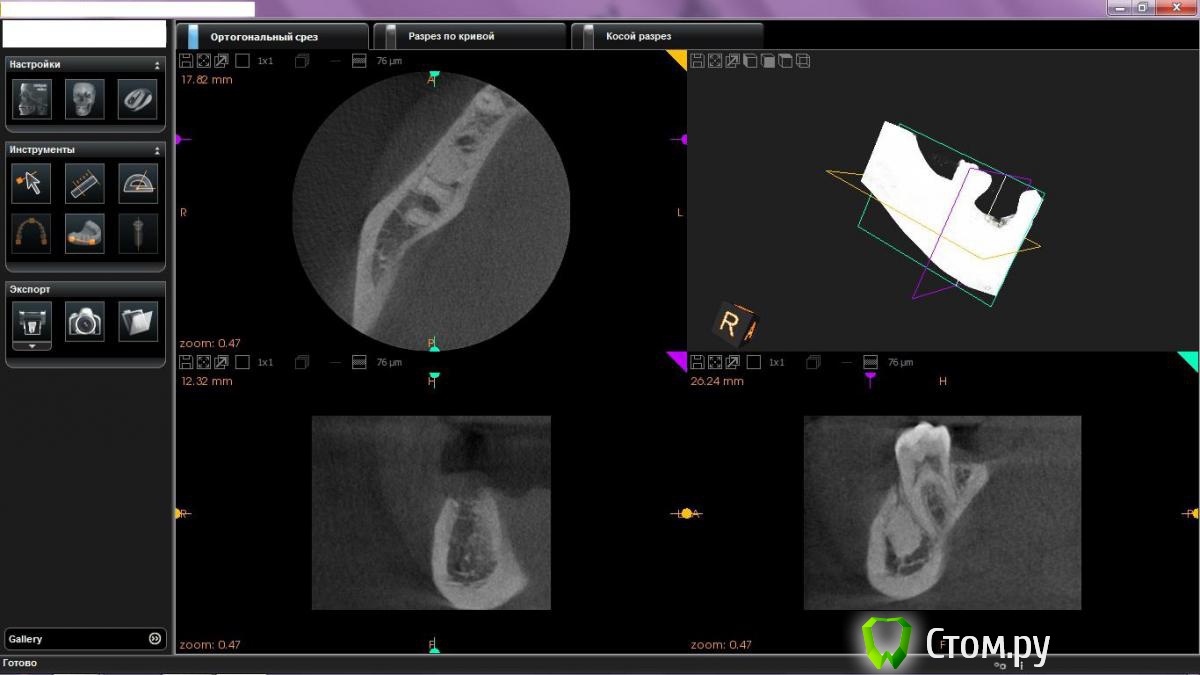

ssswww Опубликовано 3 января, 2014 Автор Поделиться Опубликовано 3 января, 2014 Не знаю всё ли здесь понятно, могу по-другому попробовать выложить. Ссылка на комментарий

ssswww Опубликовано 3 января, 2014 Автор Поделиться Опубликовано 3 января, 2014 Вот ещё. Ссылка на комментарий